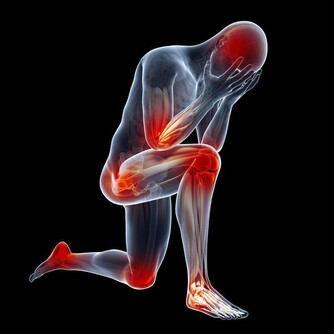

中風:引起手麻的另一常見疾病便是中風 了。

《衛生寶鑑‧中風門》曾說:「凡人初覺大指、次指麻木不仁或不用者,

三年之內有中風之疾。」須預防之:宜慎起居,節飲食,遠房幃,闊情志。

雖然手指麻木不 一定會發生中風,但對於年齡在40歲以上的中老年人來說,

如果經常出現頭痛、眩暈、頭重腳輕、肢體麻木、舌頭髮脹等症狀,

且患者平時又有高血壓、高血脂、 糖尿病、腦動脈硬化等疾病時,

應多加以注意,警惕中風的發生。